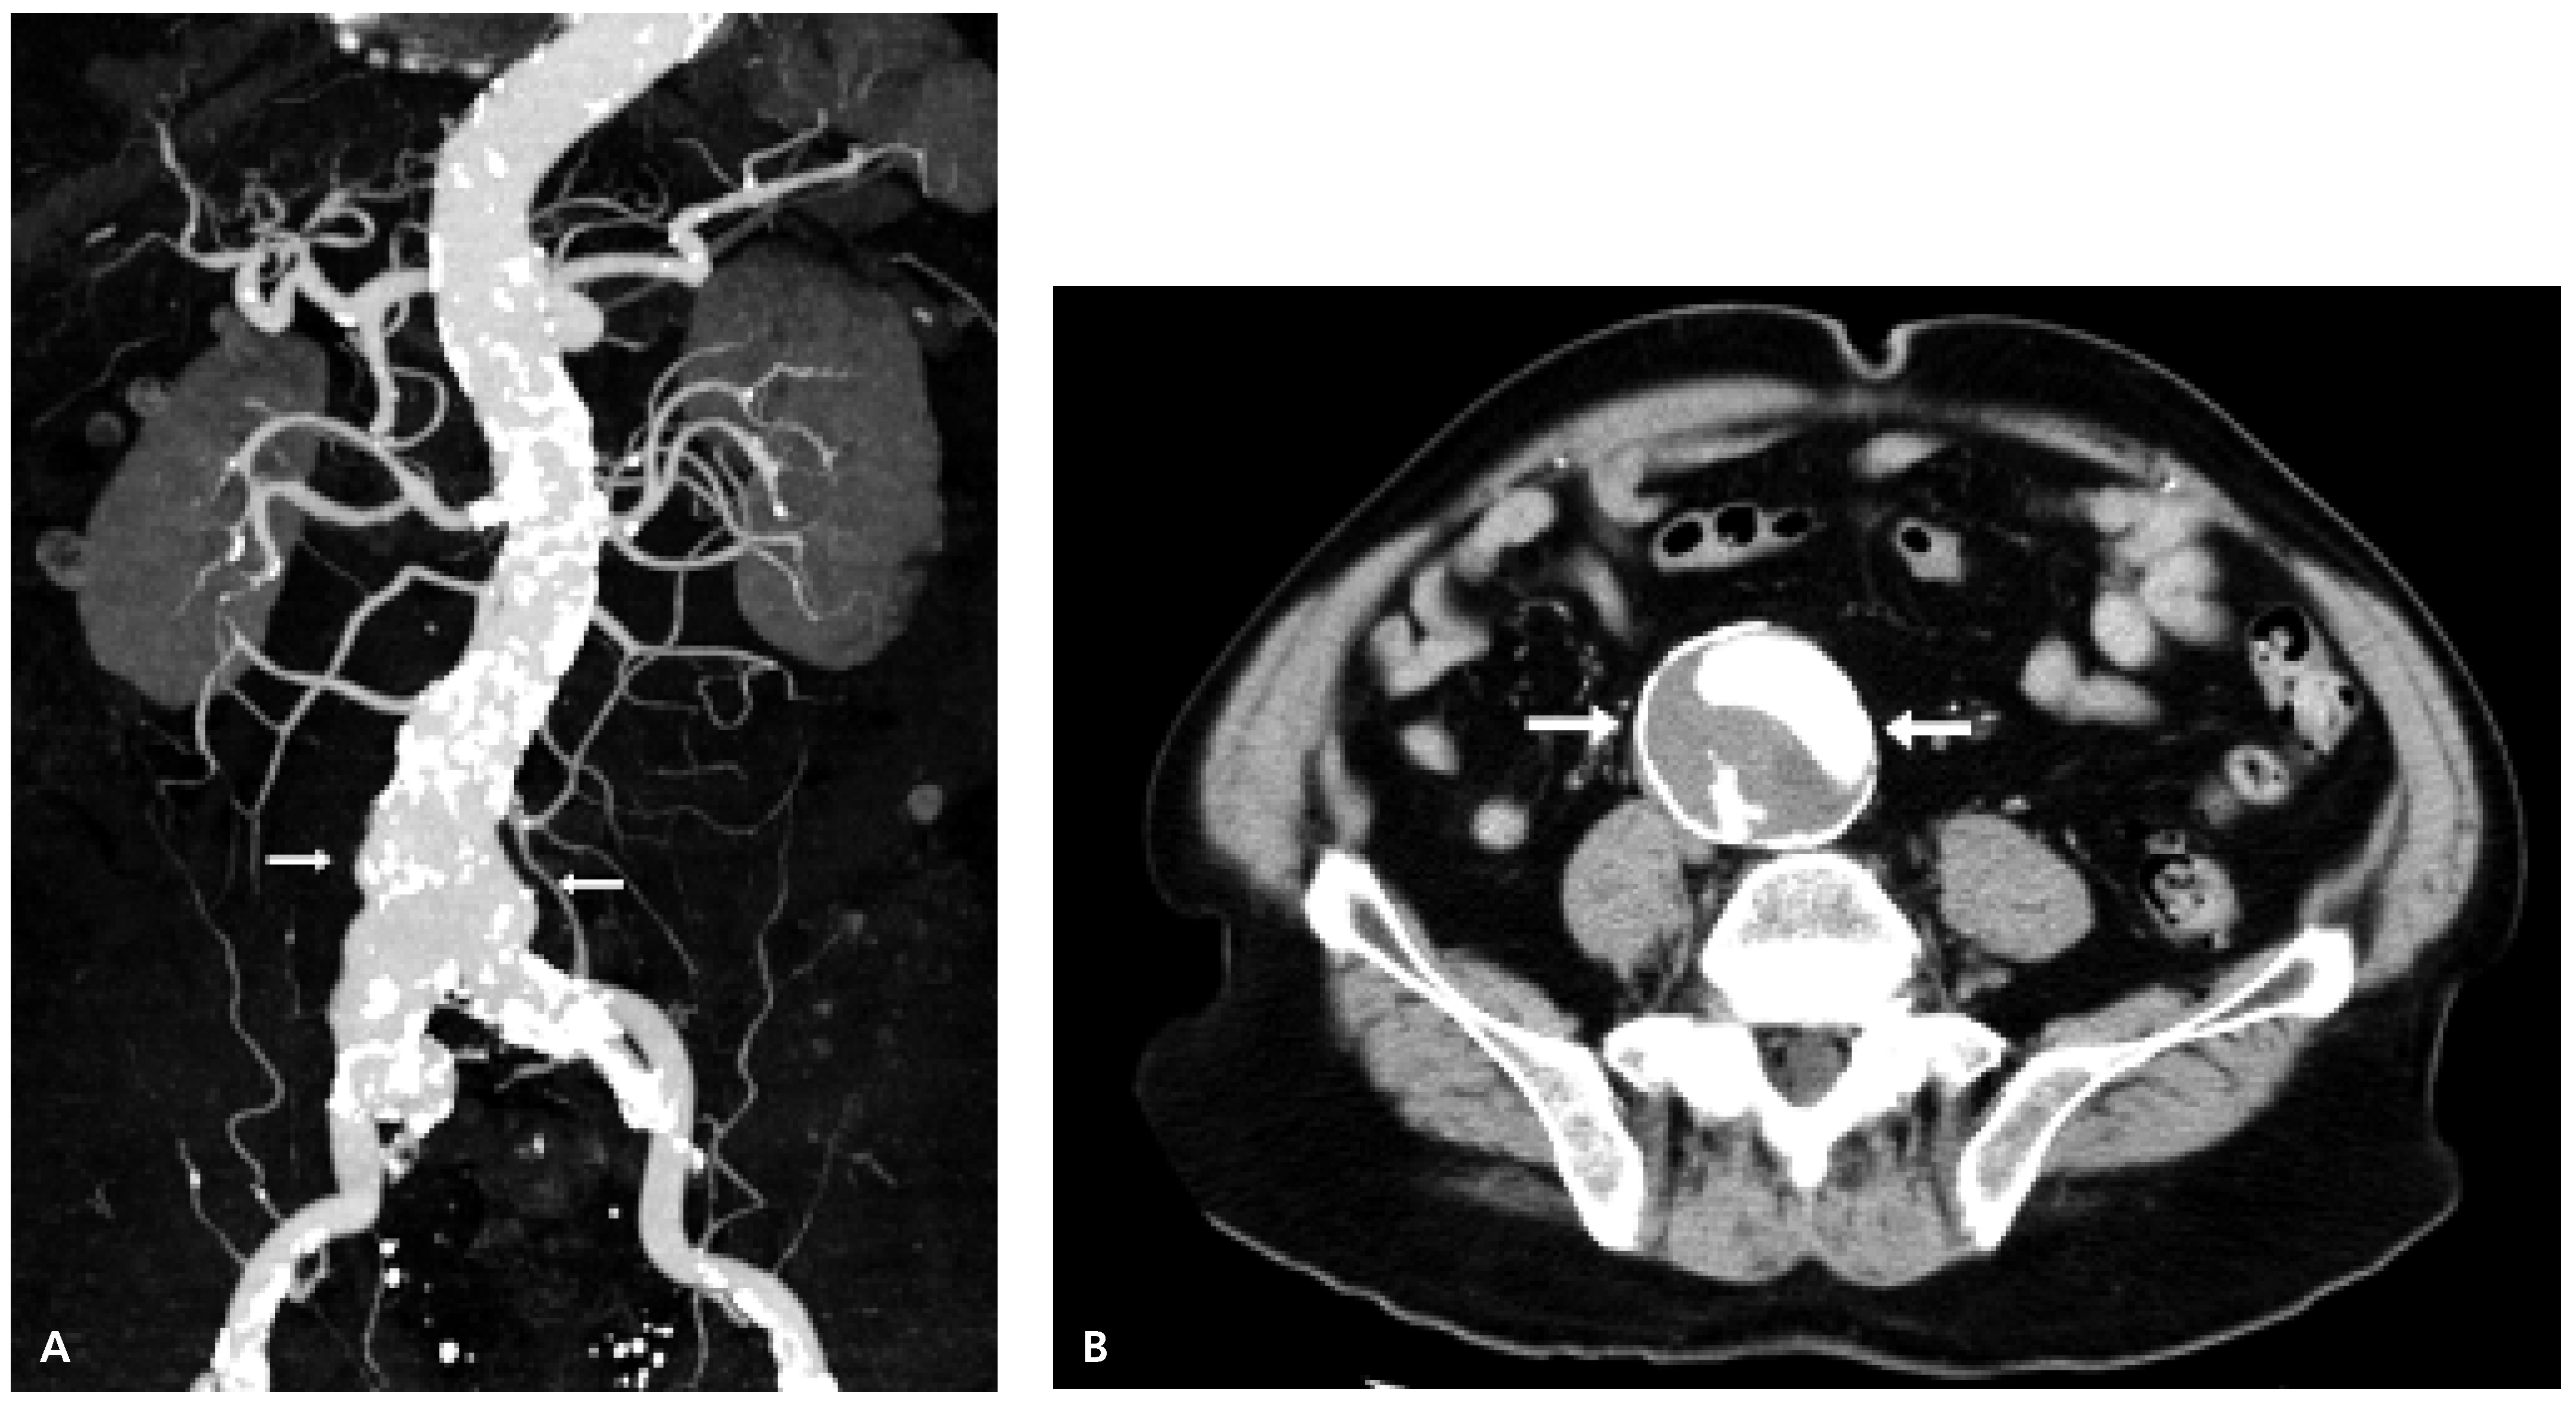

Severe Coronary Artery Ectasia and Abdominal Aortic Aneurysm

Case Report